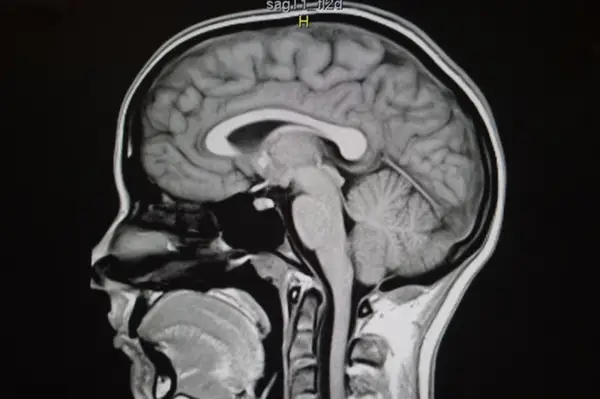

Một bộ não bình thường Hình ảnh cộng hưởng từ của một bộ não bình thường.